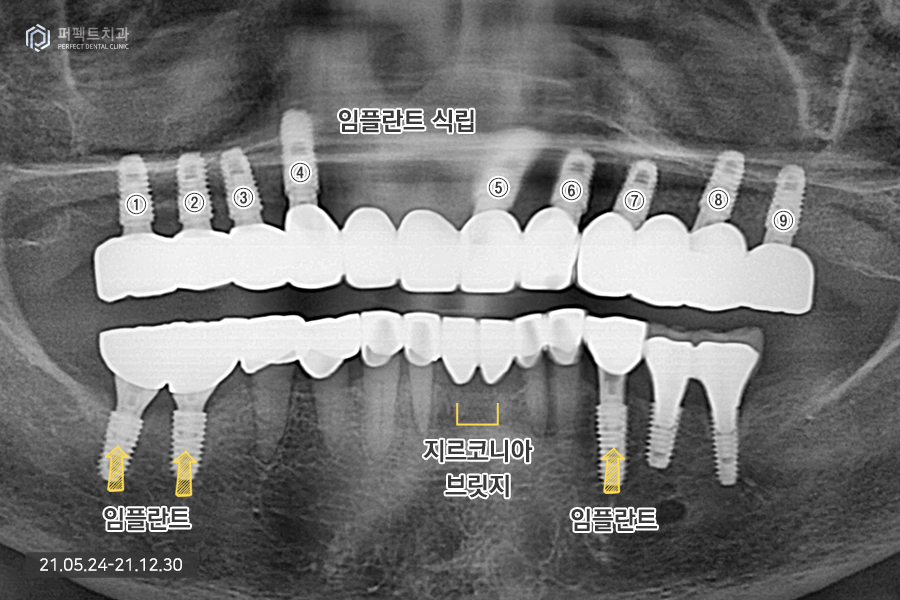

윗니의 경우 치아가 전혀 없기 때문에 9개의 임플란트를 식립하였는데 이처럼 많은 양의 임플란트를 식립하는 경우 상황에 맞게 진료를 하게 됩니다.

일반적으로 위, 아래 14개의 치아, 총 28개의 치아가 있는데 전체 치아를 완성하기 위해서 최소 6개의 임플란트를 식립해야 하며 많은 경우 10개 혹은 그 이상의 임플란트를 식립하기도 합니다.

위 환자분의 경우 뼈가 굉장히 약한 뼈이기도 하고 골다공증도 있으셔서 심을 수 있는 곳에 가능한 많은 임플란트를 식립하기로 하였습니다. 완성된 사진을 보면 더 명확히 아실 수 있는데요.

전악임플란트를 하신 부분을 확인해보시면 세덩어리로 완성을 했습니다. 오른쪽 파랗게 보이는 부분은 홀을 임시로 메워둔 상태입니다. 완성된 사진을 보시면 잘 치료된 것을 보실 수 있을 것입니다.

그 이유는 첫번째, 임플란트 식립 환경이 좋지 않았기 때문입니다. 환자분은 골다공증도 있으셨고 뼈가 너무 물러서 임플란트를 식립할 수 없는 자리도 많이 있었기 때문입니다. 그러다보니 환자분께서는 임플란트를 식립할 수 있는 곳에는 임플란트를 식립하길 원하셨고 이로 인해 9개의 임플란트 식립, 5개의 치아를 걸어서 14개의 완성된 치아를 갖게 되었습니다.

그리고 두번째로 어려운 점은 위에 치아가 없기 때문인데, 이런 경우 위아래 높이의 기준이 사라지게 됩니다. '고합고경'이라는 말을 쓰는데 위아래 치아가 맞물리는 높이를 설정하는데 굉장히 어려움을 겪게 됩니다. 치아가 한두개만 있더라도 위아래가 물리는 기준점이 있는데 환자분의 경우 1) 치아가 하나도 없고, 2) 틀니 사용도 하지 않기 때문에 위아래 높이를 맞추는 일이 어렵습니다.

그렇지만 요즘에는 디지털화 되고 3d 스캐너와 3d CT를 사용해 환자분이 가지고 있는 처음 높이를 그대로 가지고 올 수 있습니다. 예전 방식 보다는 조금 더 쉽게 완성을 할 수 있었고 임시치아도 다 만들어서 한번 써보았기 때문에 높이가 완전히 맞은 다음 최종 보철을 완성하는 과정을 거치게 되었습니다. 총 치료기간은 7개월로 깔끔하게 마무리가 되었으며 지금도 만족하면서 잘 사용하고 계십니다 ^^